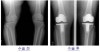

선 자세에서 무릎을 쭉 펴고 AP view를 찍으면 관절관격이 좁아진 것이 보입니다.

퇴행성 관절염의 이상 소견은 비대칭적 관절간격 좁아짐(joint space narrowing), 골경화(subchondral bone sclerosis), 관절주위낭종(subchondral cyst), 골극(osteophyte, spur)입니다.

추가로 무릎을 40도 정도 구부리고 선 자세에서 AP view를 찍으면 경골과 대퇴골의 서로 다른 체중 부하부위가 보이므로 관절면의 좁아짐을 관찰할 수 있어서, 관절염에서 가장 감수도가 높은 검사법입니다.

X-ray : 무릎 관절염(Knee Osteoarthritis)